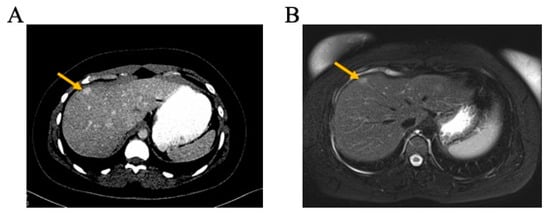

- Vassallo, L.; Fasciano, M.; Fortunato, M.; Orcioni, G.F.; Vavala, T.; Regge, D. Focal nodular hyperplasia after oxaliplatin-based chemotherapy: A diagnostic challenge. Radiol. Case Rep. 2022, 17, 1858–1865. [Google Scholar] [CrossRef]